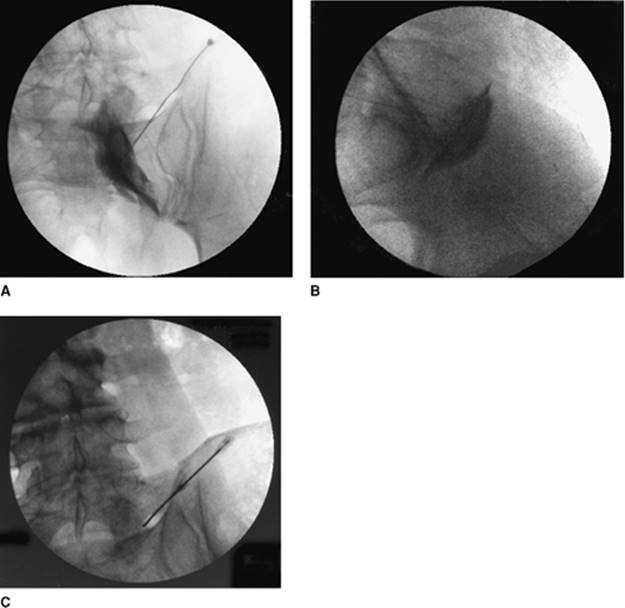

Approach and Technique: The lumbar region is prepared and draped using sterile techniques. Using fluoroscopy in a 10° to 20° cephalad caudad and ipsilateral 15° to 30° oblique view, identify the triangular shape formed by shadows of L5 transverse process and sacral and iliac crest. Using a gun-barrel technique (i.e., the needle parallel to x-ray beam), take frequent anteroposterior views (Fig. 63-7A with dye, Fig. 63-7C without dye) to assess direction and lateral views (Fig. 63-7B) to assess depth. The tip of the needle is placed at the anterolateral upper edge of the sacral promontory in the lateral view and medial to the facet line in the anteroposterior view. Confirm placement using Isovue-200, 3 to 5 mL, and take anteroposterior and lateral views.

Figure 63-7. Hypogastric plexus block.

Approach and Technique: The lumbosacral region is prepared and draped using sterile techniques. The sacrococcygeal junction and the tip of the coccyx are located using fluoroscopy. The midline is identified and a skin wheal using a 25-gauge needle with 1% lidocaine is performed. The spinal needle is advanced perpendicular to the skin at the sacrococcygeal junction, and its tip is placed anterior to the sacrococcygeal junction using fluoroscopy, confirming appropriate position using anteroposterior and lateral views. After careful aspirate for blood, air, or feces, and after negative aspiration, the radiocontrast dye is injected to confirm the spread of contrast medium just anterior to the sacrococcygeal junction. This is then followed with injection of the local anesthetic mixture/phenol. Figure 63-8 presents the anteroposterior (A) and lateral view (B).

Figure 63-8. Anteroposterior (A) and lateral (B) view of ganglion impar block.